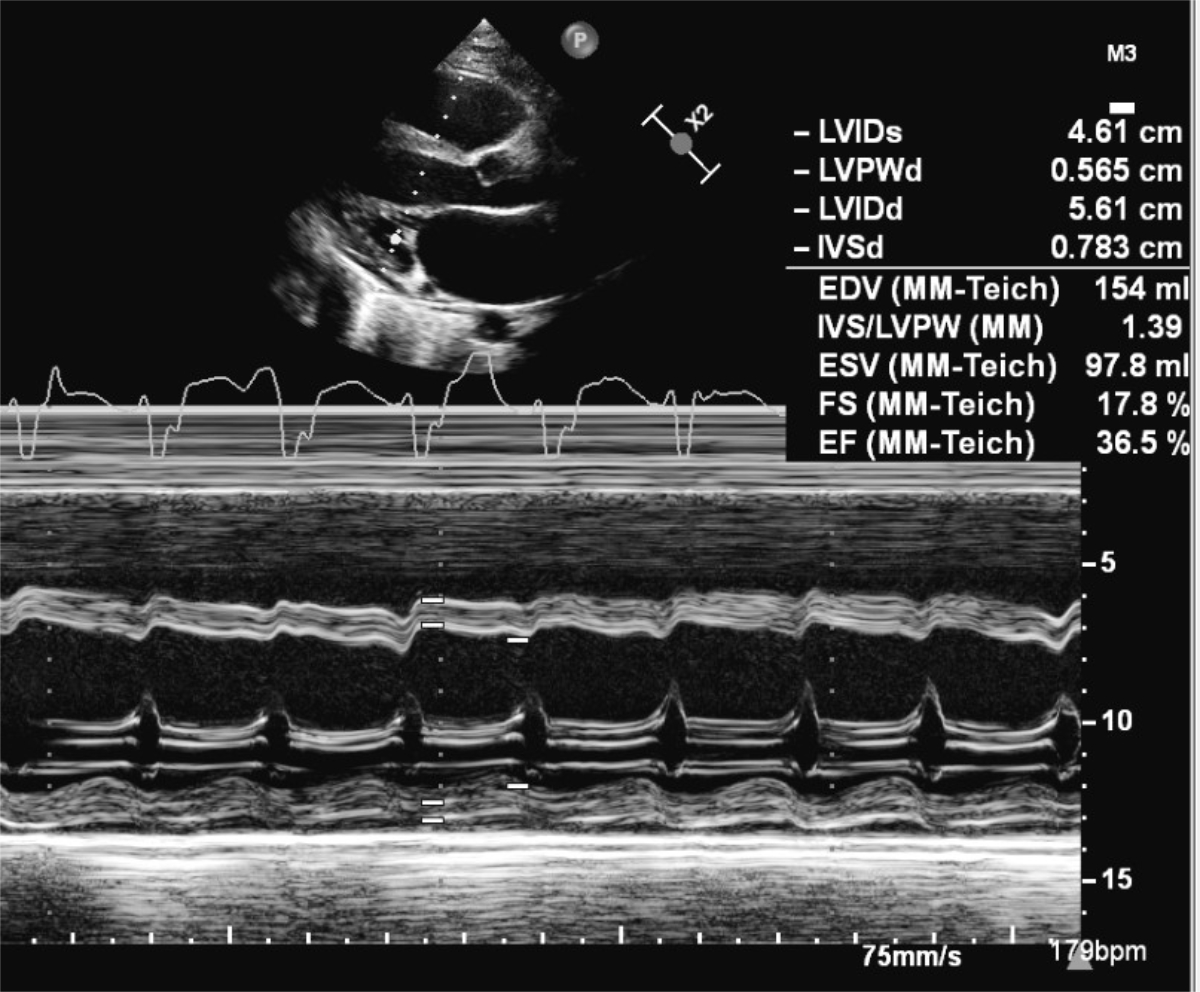

Thirteen days after the positive PCR test, he was admitted to our cardiac paediatric intensive care unit in decompensated cardiogenic shock due to a monomorphic ventricular tachycardia (fig. 1) and moderately to severely reduced biventricular cardiac function with a biplane left ventricular ejection fraction of 20%, right ventricular fractional area change of 12%, and fractional shortening of 18% (fig. 2). He was afebrile and the second nasophyrangeal swab for SARS-CoV-2 PCR was still positive after admission. On admission troponin-T was 48 ng/l (reference <14 ng/l), creatinine kinase (CK) 201 U/l (<168 U/l), CK-MB 7.3 µg/l (<6.2 µg/l), and N-terminal-pro-B-type natriuretic peptide (NT-pro-BNP) 10,738 ng/l (<360 ng/l). There were no signs of thrombocytopenia, increased C-reactive protein, and no elevation or decrease of white blood cells or abnormalities in the white blood cells subsets. The clinical status showed no lymphadenopathy, conjunctivitis, mucus membrane changes, rash, or swollen hands and feet. The ventricular tachycardia was recurrent and required electric cardioversion on three occasions within the first 24 hours, in addition to amiodarone therapy. The severely reduced biventricular myocardial function led to progressive pulmonary oedema, pericardial and pleural effusions, and oxygenation failure requiring intubation, high ventilator pressures, inhaled nitric oxide, and bilateral chest drains. A suspected secondary bacterial pneumonia due to the severe clinical (septic) course was treated empirically for 5 days with antibiotics, although cultures remained negative. He was not given additional antiviral therapy due to limited evidence and spontaneous clinical recovery. Progressive low cardiac output with cardiogenic shock and multi-organ dysfunction (acute renal failure RIFLE-I [11], liver dysfunction with coagulopathy) required high-dose inovasodilators. On day 4, creatinine kinase (maximum 2040 U/l) and myoglobin (maximum 669 ng/ml) were at their highest level. The following ECG revealed altered repolarisation (negative T wave up to V6), but no signs of acute infarction. The myocardial function measured by echocardiography improved rapidly, with a left ventricular ejection fraction of 40–50% within 48 hours of admission. After 5 days of inotropic treatment and mechanical ventilation he was transferred to the cardiac ward under treatment with oral diuretics, enalapril, and amiodarone.

Figure 2 Transthoracic 2D echocardiography at admission showed severe reduced left ventricular function on M-mode with a fractional shortening of 18%.